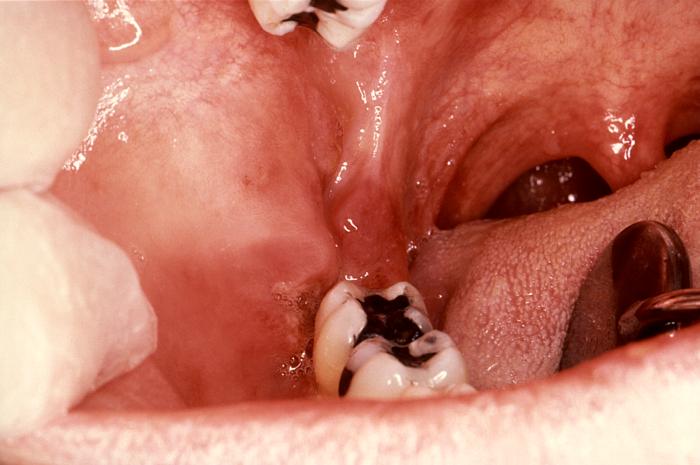

Este tumor es multifocal y

en la boca puede observarse varias lesiones en paladar y/o encía, aunque lo

más frecuente es que el paciente tenga otras lesiones en piel de

extremidades superiores, torax

y cara.

Sarcom de Kaposi

en zona de trígono retromolar |